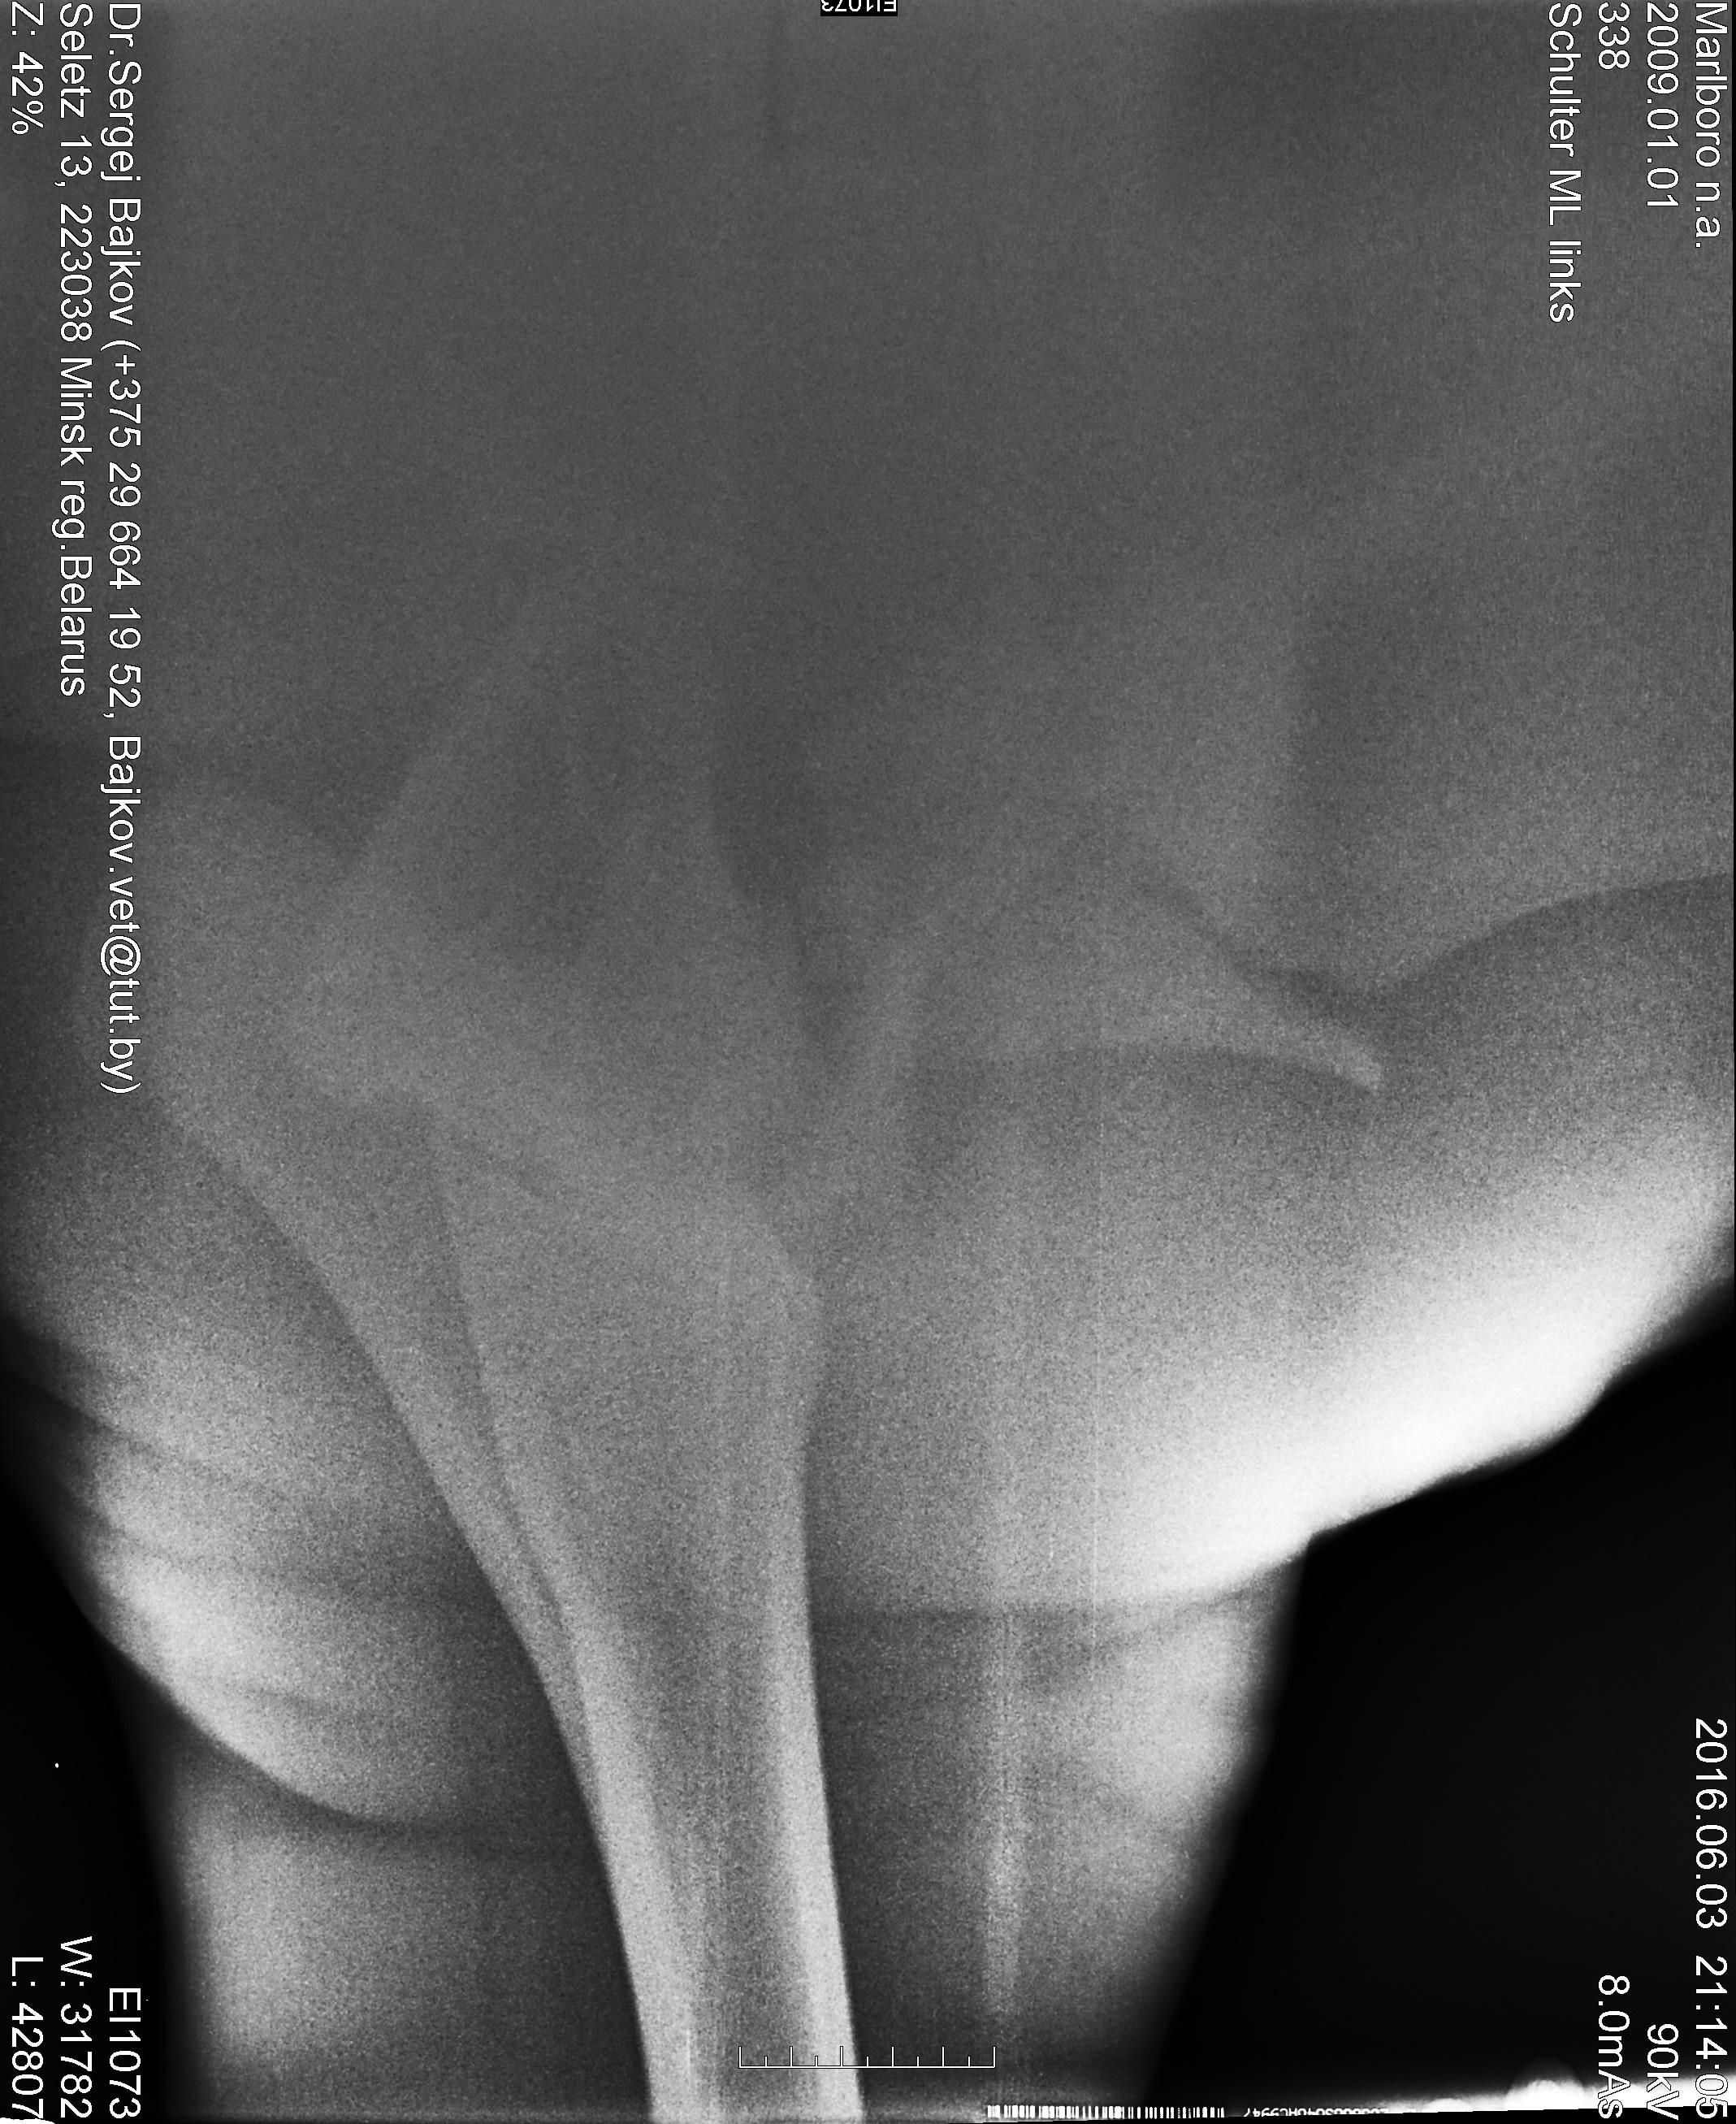

Собственно, еще до первого рентгена его смотрела наш врач. И потом всю дорогу готовила меня морально "надо делать снимок, но диагноз неблагополучный". После снимка, другой уже врач -- цитирую -- "п...ц. Кость в хлам".

И тоже однозначно -- усыплять.

Ночь никто не спал, все думали, какие могут быть варианты. Той ночью я придумала конструкцию, как перевезти лошадь с такой травмой, например, в московскую клинику. Отослала снимки кому только можно.

И -- нам не отказали. Запросили дополнительные снимки. Анатомические атласы. Кость с анатомички.

Когда вскрыли плечо и увидели второй перелом, и никак не удавалось совместить кости, хирург спросил -- сколько у нас времени? Имея ввиду наркоз.